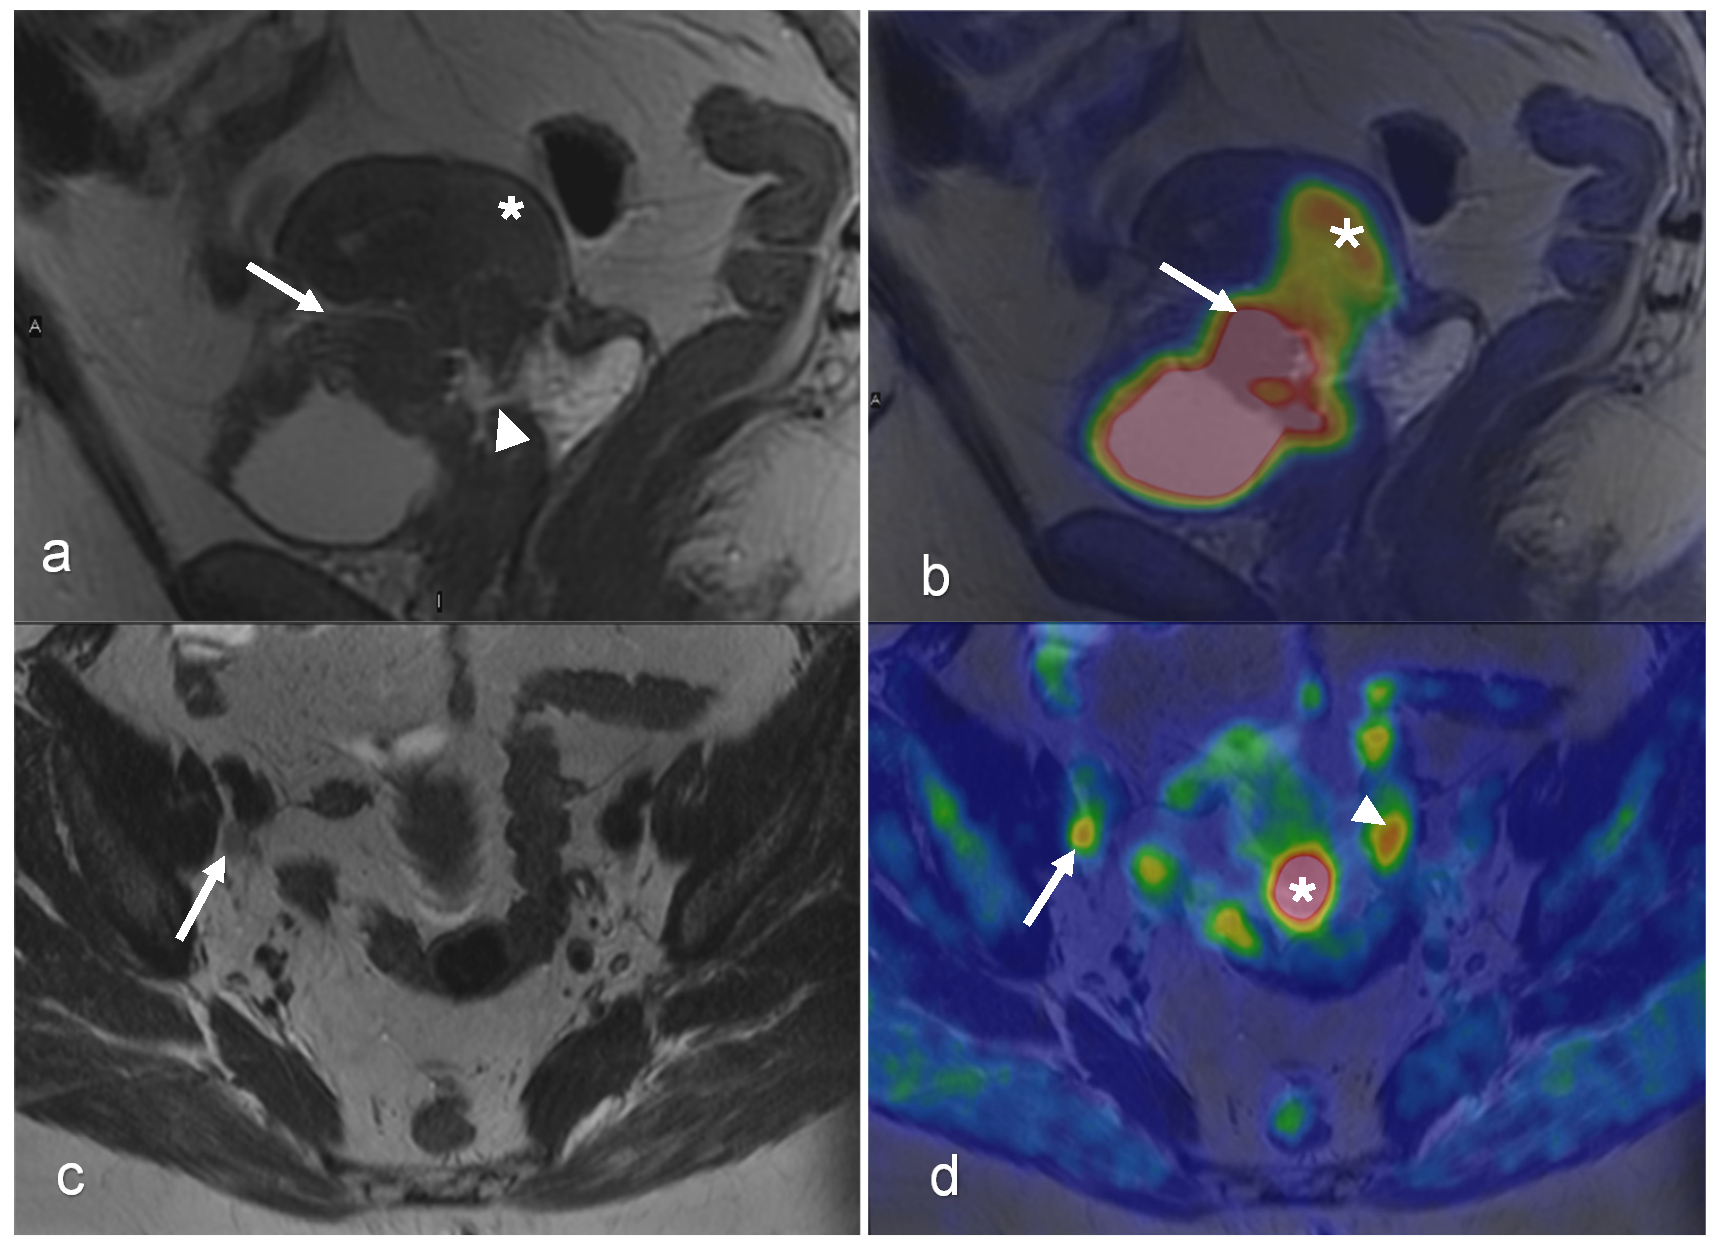

- Chow, L.; Tsui, B.Q.; Bahrami, S.; Masamed, R.; Memarzadeh, S.; Raman, S.S.; Patel, M.K. Gynecologic tumor board: A radiologist’s guide to vulvar and vaginal malignancies. Abdom. Radiol. 2021, 46, 5669–5686. [Google Scholar] [CrossRef] [PubMed]

- McGettigan, M.; Zulfiqar, M.; Shetty, A.S. Imaging of Vaginal and Vulvar Malignancy. Radiol. Clin. N. Am. 2023, 61, 651–670. [Google Scholar] [CrossRef]

| Vaginal/Vulvar | Benefit(s) | Helpful in determining disease extent and nodal/metastatic involvement [42] Useful for identifying distant metastases, including pulmonary and bony metastases in vulvar cancer [42] | The modality of choice for locoregional assessment, detection of primary and metastatic cancer, and treatment response The most sensitive modality for detecting pelvic lymph node involvement [42] | Useful for radiation therapy planning [43], assessing response to neoadjuvant chemotherapy and guide patient management Evaluation of nodal and distant metastatic involvement in staging of recurrent vaginal cancer [42] | Helpful in for detecting vulvar cancer recurrences and distant metastases [42] |

| Pitfall(s) | Difficulty in assessing lymph node involvement, especially in small or micro-metastatic nodes Inability to determine local tumor staging due to low soft tissue contrast [42] | Limited value in detecting lymph node metastases ≤ 5 mm and necrotic lymph nodes False-positive (e.g., inflammatory lymph node) [23] |